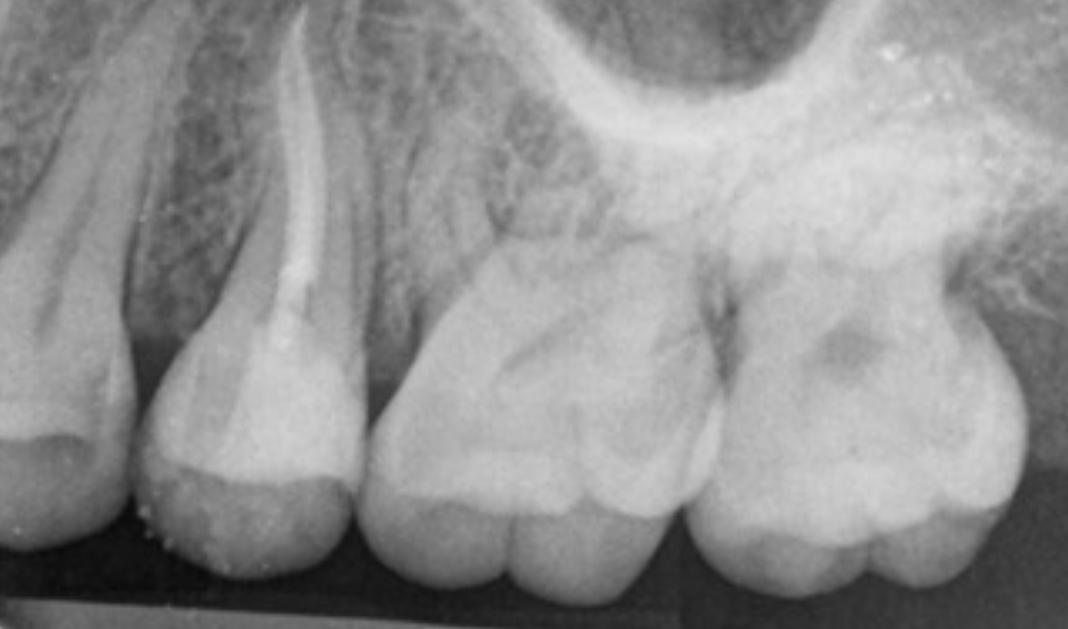

the case: Patient had hidden interproximal caries on upper first pre-molar.

Fig. 1: Initial situation. Fig. 2: X-ray showed hidden caries at the distal side of the upper first pre-molar. Fig. 3: Isolation with rubber dam. Fig. 4: Preparation. Hidden Proximal Caries | Posterior continues next page >>>